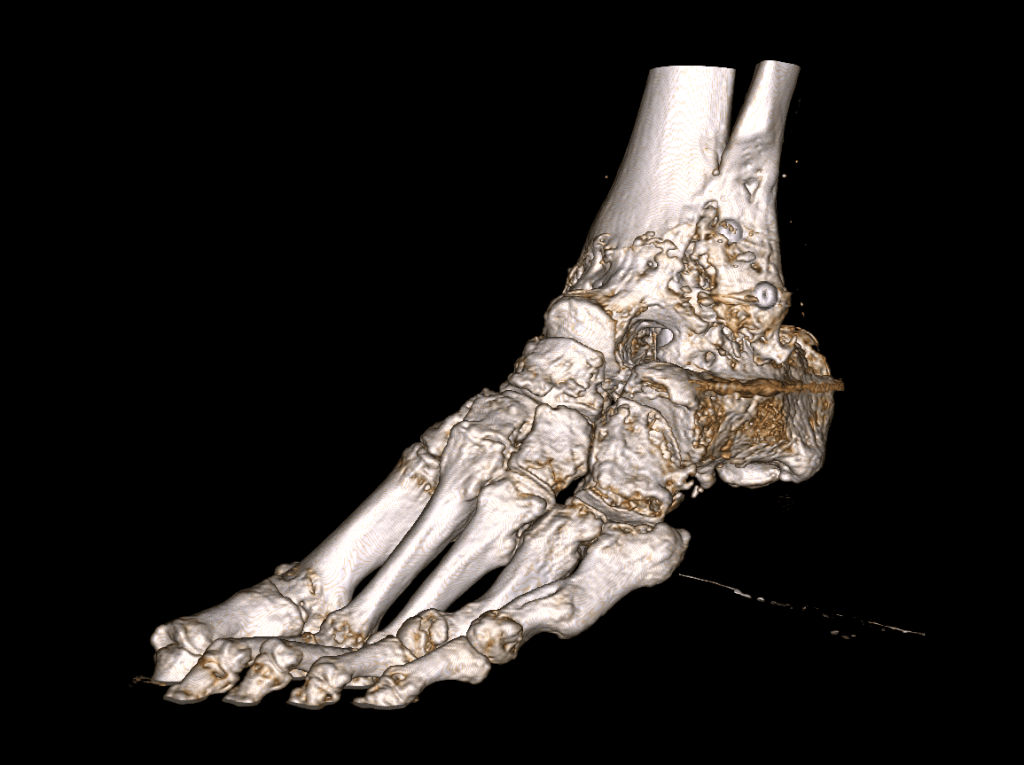

La impresión 3D ha tenido gran acogida en trauma y ortopedia por ser una gran ayuda para entender la relación entre todos las estructuras y para planear las cirugías.

Este es el caso de un pie que había sufrido un trauma y ya había sido intervenido, pero querían hacer otra cirugía para corregir los resultados después de un periodo de curación.

Mediante el uso de segmentación médica se pudo extraer la información del tejido oseo y corregir los artefactos de las imágenes medicas.

Con ese modelo, se procedió a imprimir el modelo